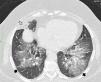

La tomografía computarizada de alta resolución torácica muestra una consolidación grasa peribronquial en el lóbulo medio (flecha blanca). Extensa representación de opacificación en vidrio esmerilado con una sutil reticulación interna (patrón en empedrado) hasta los espacios pleurales (flechas negras), 8 meses después de la suspensión de la vaselina de petróleo y la terapia de esteroides (prolongada durante 6 meses).